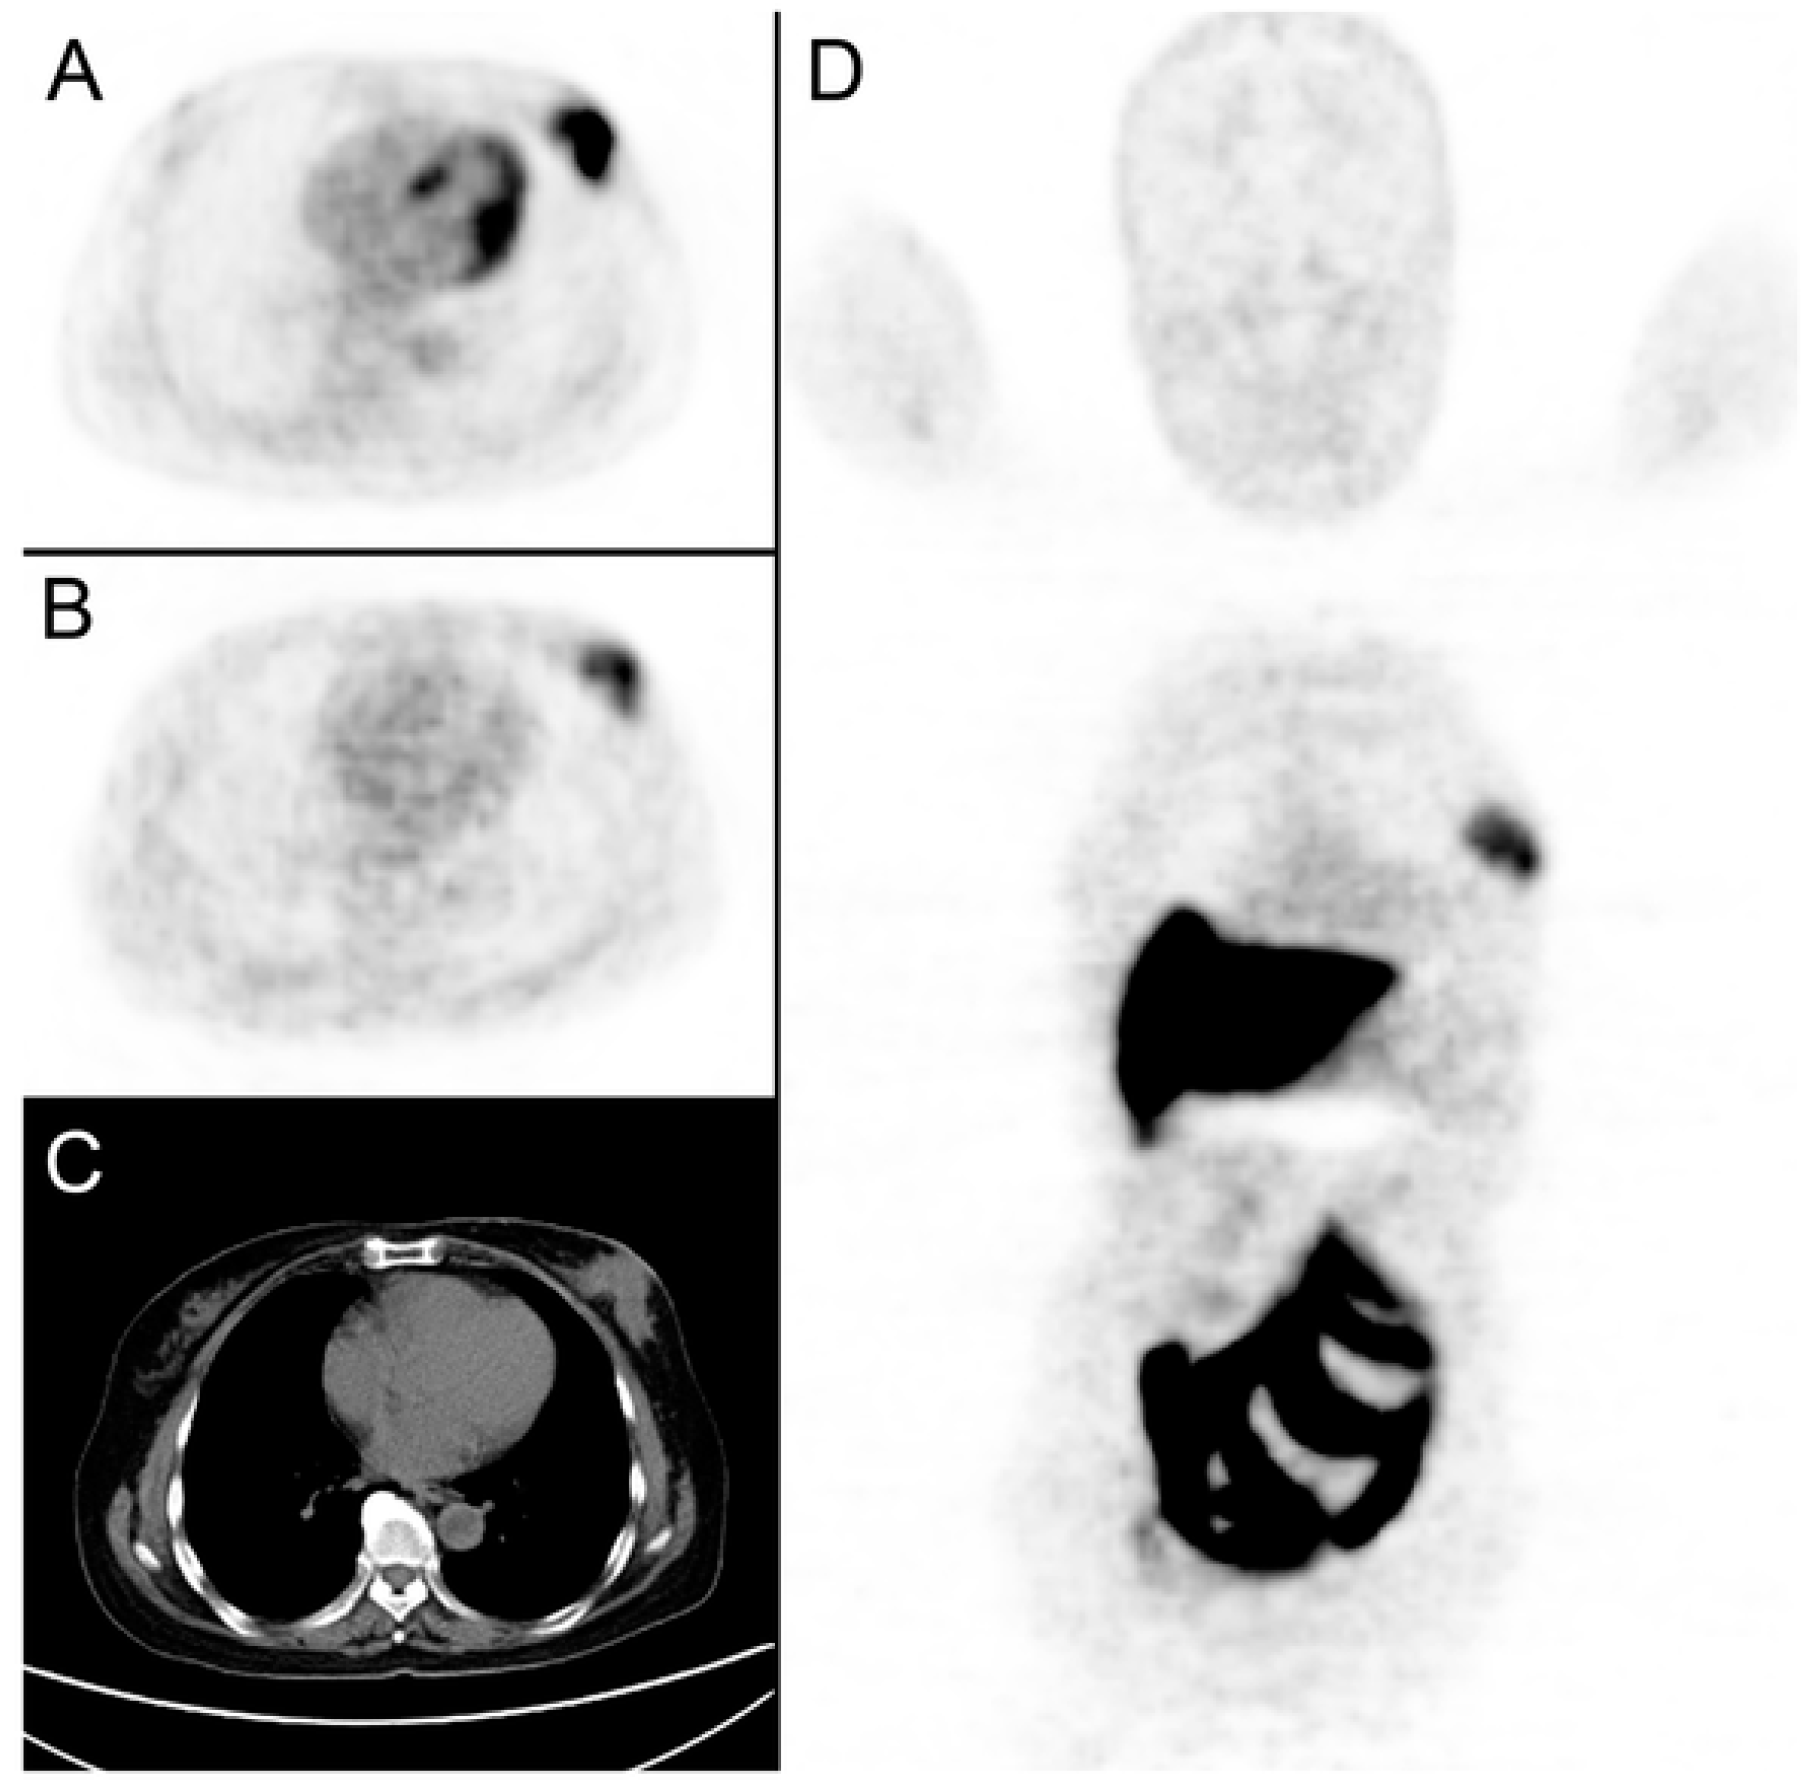

- Yang, Z.; Sun, Y.; Xue, J.; Yao, Z.; Xu, J.; Cheng, J.; Shi, W.; Zhu, B.; Zhang, Y.; Zhang, Y. Can Positron Emission Tomography/Computed Tomography with the Dual Tracers Fluorine-18 Fluoroestradiol and Fluorodeoxyglucose Predict Neoadjuvant Chemotherapy Response of Breast Cancer?—A Pilot Study. PLoS ONE 2013, 8, e78192. [Google Scholar] [CrossRef] [PubMed]